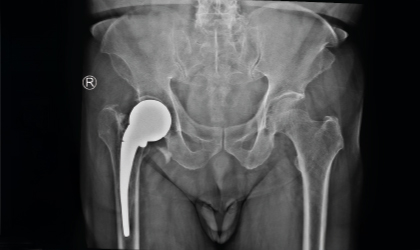

This 83 year old gentle man had a hip fracture 25 years ago. This became painful recently. He had an interesting (to the surgeons!) complication with a fracture of the stem in 3 places. This was revised to a total hip replacement. We used a longer stem to bypass the defects. He is mobile with a stick.